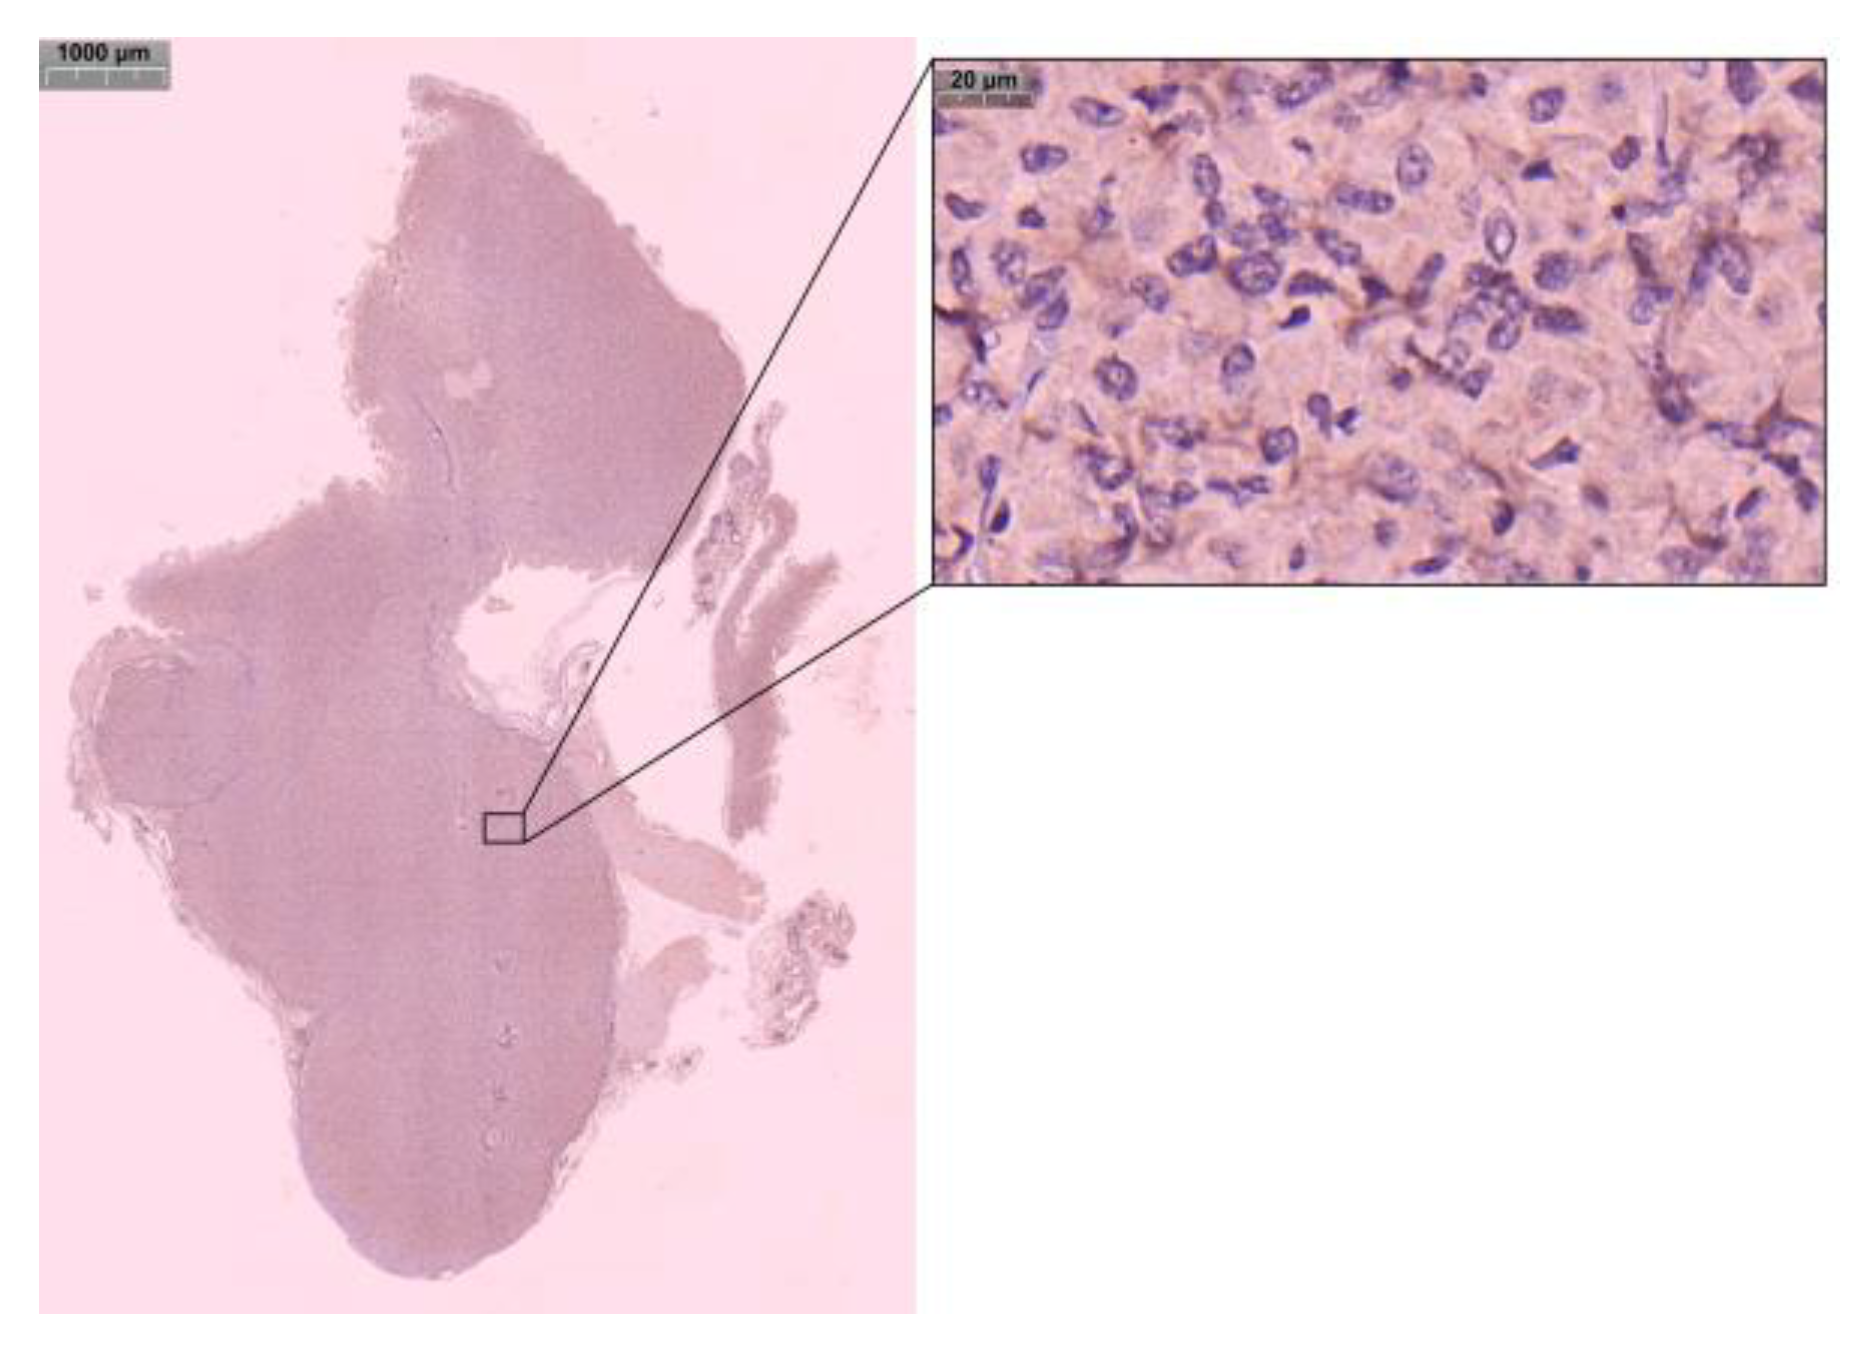

2.9. Immunohistochemical

4.12. Immunohistochemical Staining